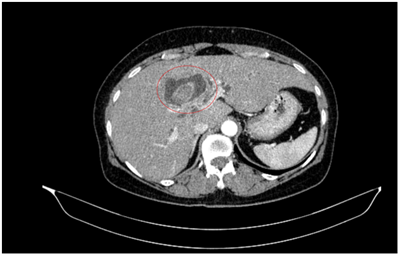

UNG THƯ BIỂU MÔ TẾ BÀO THẬN

Ung thư thận là loại ung thư thường gặp đứng thứ 14 trên toàn cầu, với hơn 430.000 ca mới được chẩn đoán vào năm 2020, và 434840 ca mắc trên toàn cầu vào năm 2022. Tỷ lệ mắc thay đổi theo khu vực địa lý, cao hơn ở châu Âu và Bắc Mỹ. Ung...